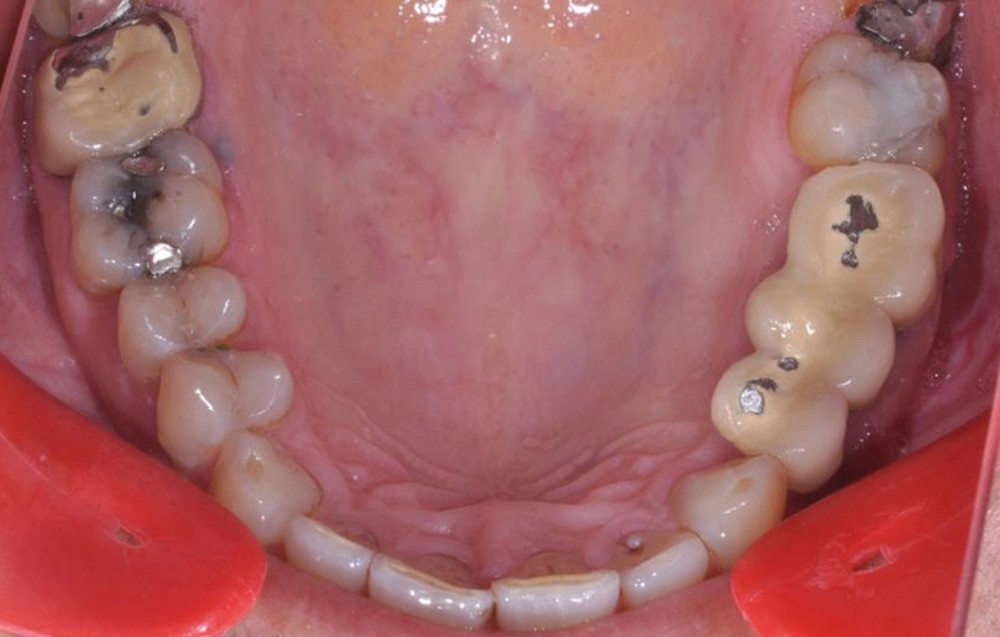

Présentation du cas clinique (fig. 1 à 3)

Le patient, âgé de 58 ans, présente un encombrement dentaire mandibulaire de 5 mm dans un contexte squelettique hypodivergent.

À la radiographie panoramique, on constate une lésion apicale sur 15 et une atteinte inter radiculaire sur 16 ainsi qu’une légère rotation de 21 sans gêne pour le patient.